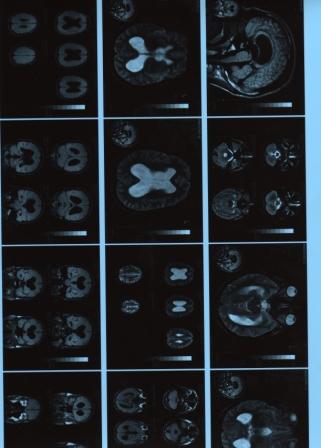

Вопрос:   -- Здравствуйте, моему мужу 28 лет, с подроскового возраста болела голова в то время он к врачам не обращался. Последние годы боль усилилась и участилась. По результатам МРТ 2 года назад Выраженная неокклюзионная внутренняя гидроцифалия, проведено несколько курсов лечения -помогает но временно. Результаты повторного МРТ неделю назад:выраженная внутренняя гидроцифалия,арезорбтивная,внутричерепная гипертензия. Формирующееся пустое турецкое седло. Без отрицательной динамики. У меня вот какой вопрос возможно ли вылечить его заболевание без оперативного вмешательства. Как попасть на консультацию в ваш институт (мы не из москвы) к какому из сотрудников вы посоветуете обратится. И сколько стоит консультация с назначением курса лечения . Спасибо очень надеюсь на ваш ответ и помощь в нашем городе нет таких специалистов. В прикрепленных фаилах снимки и курсы лечения которые назначали. Олег Антошечкин

Файл с дополнительной информацией